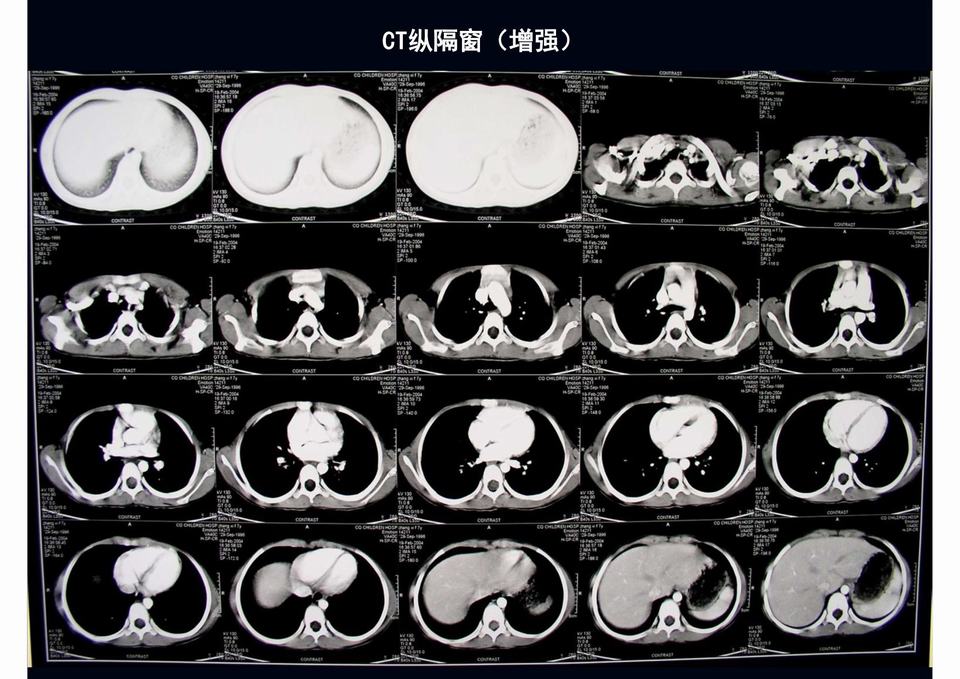

【PPT】儿童胸部影像学